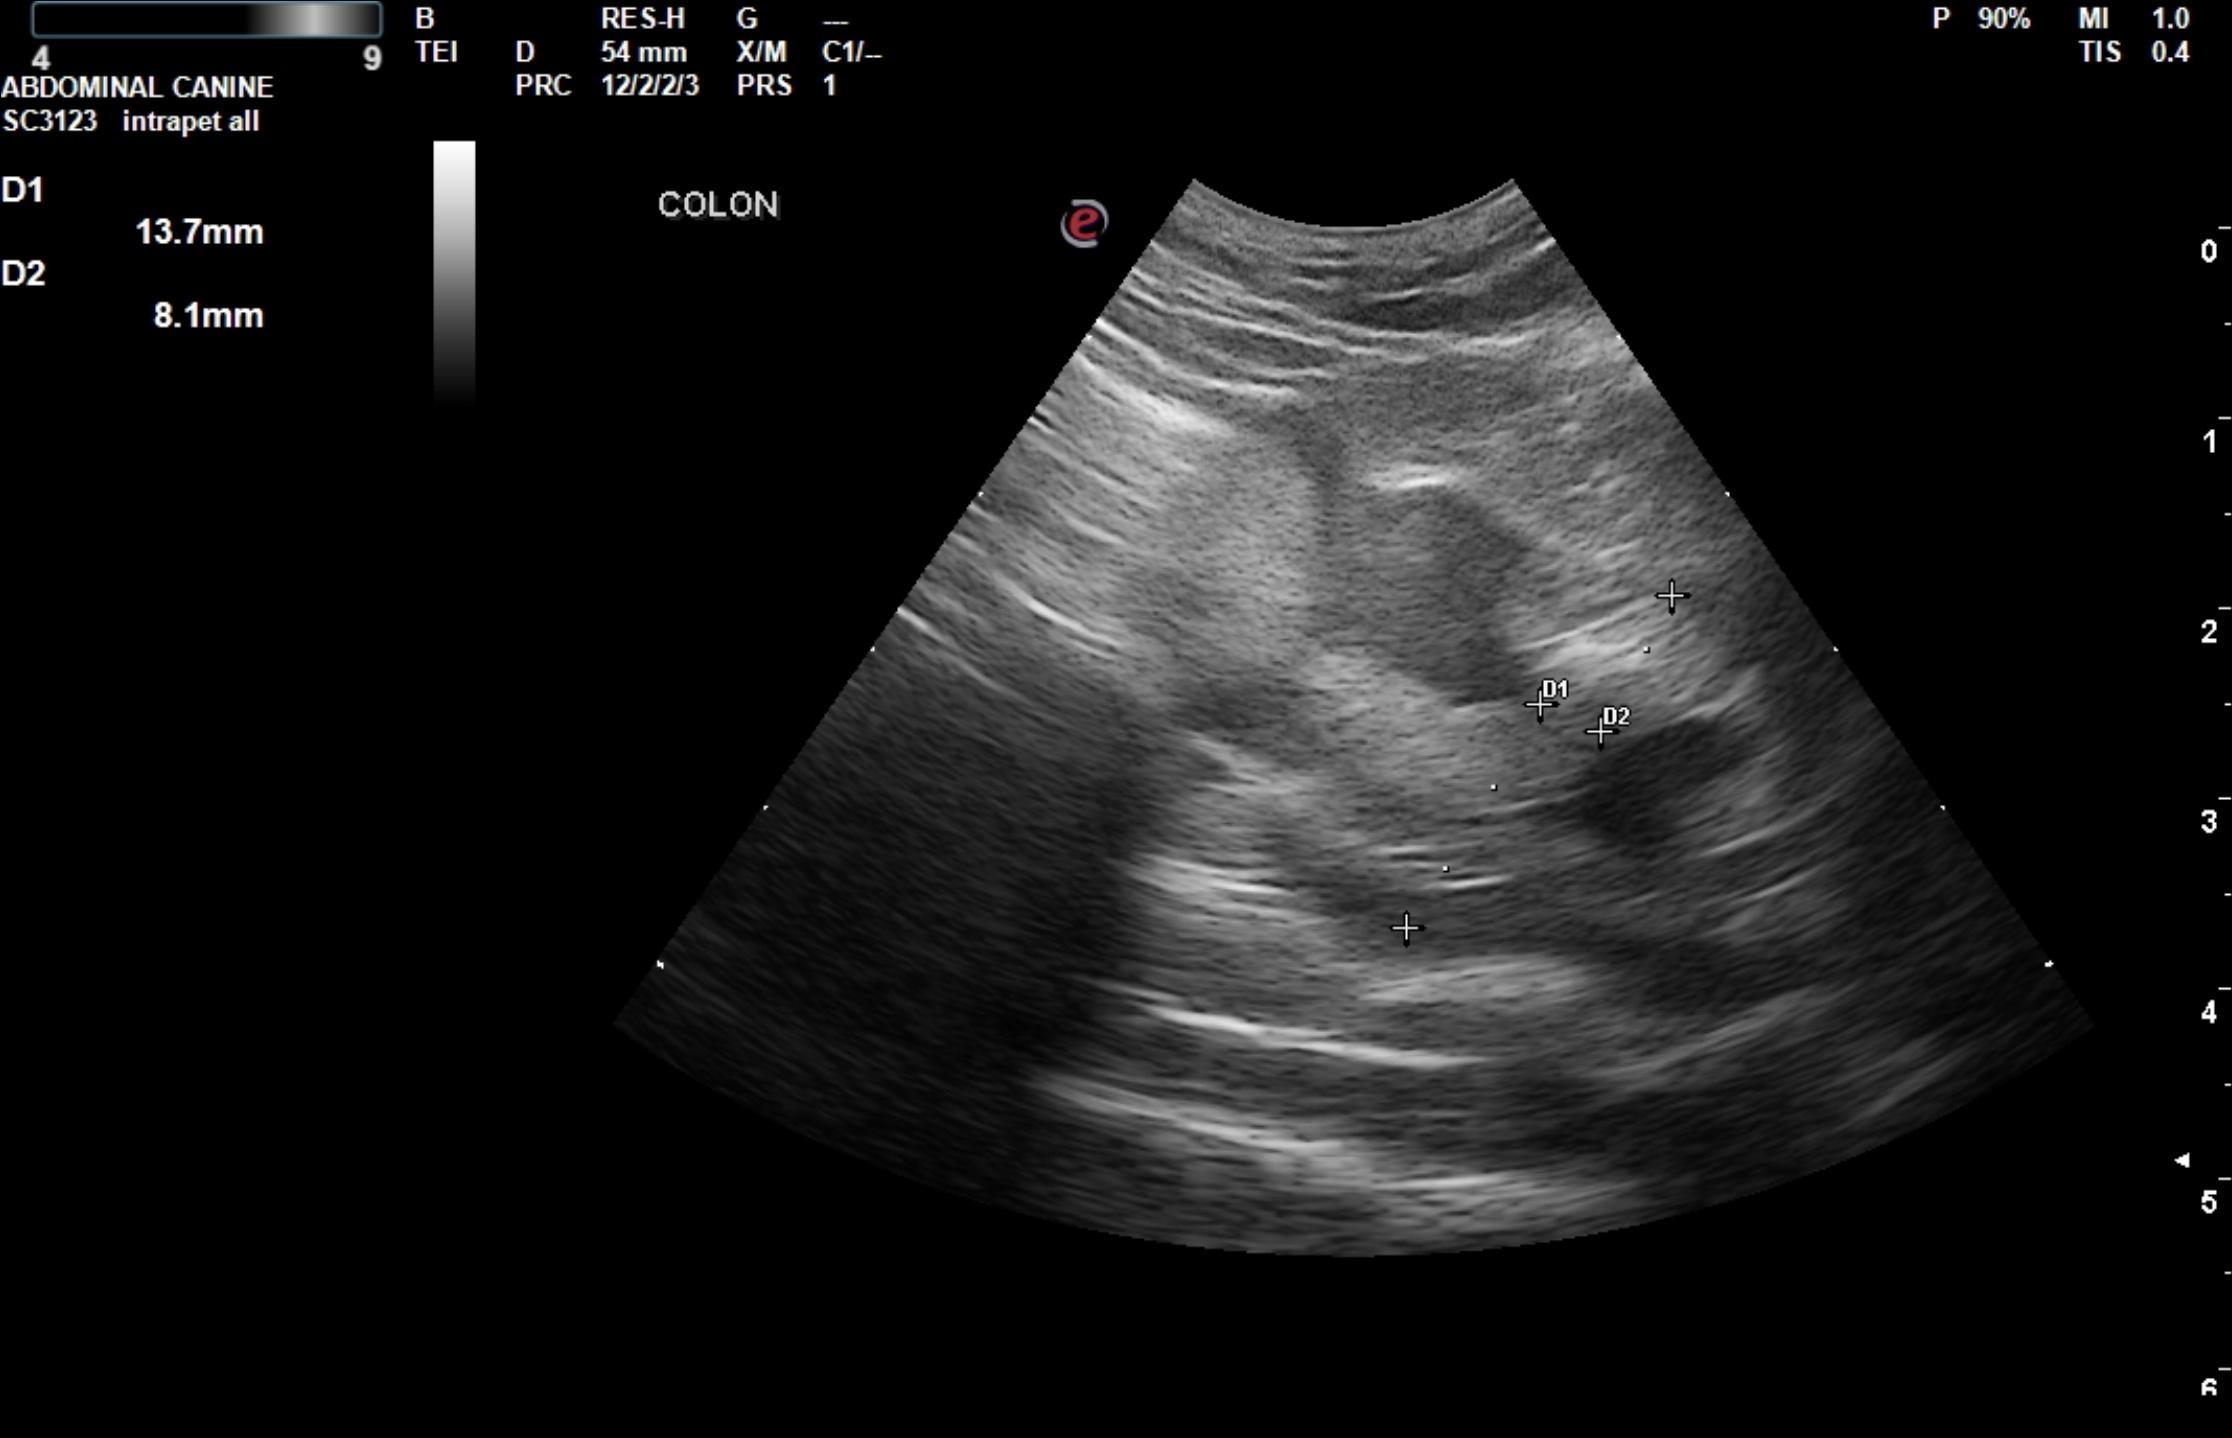

The colon in this patient revealed an approximately 2.0 x 4.0 cm concentric mass with an obstructive pattern. Hypoechoic, ill defined colonic wall was noted. Stool was obstipated from the level of the deep pelvis proximally to the ileocecal junction. The colonic mass appears to be in the distal colon in the pelvic inlet. The mass extended into the colorectal region.